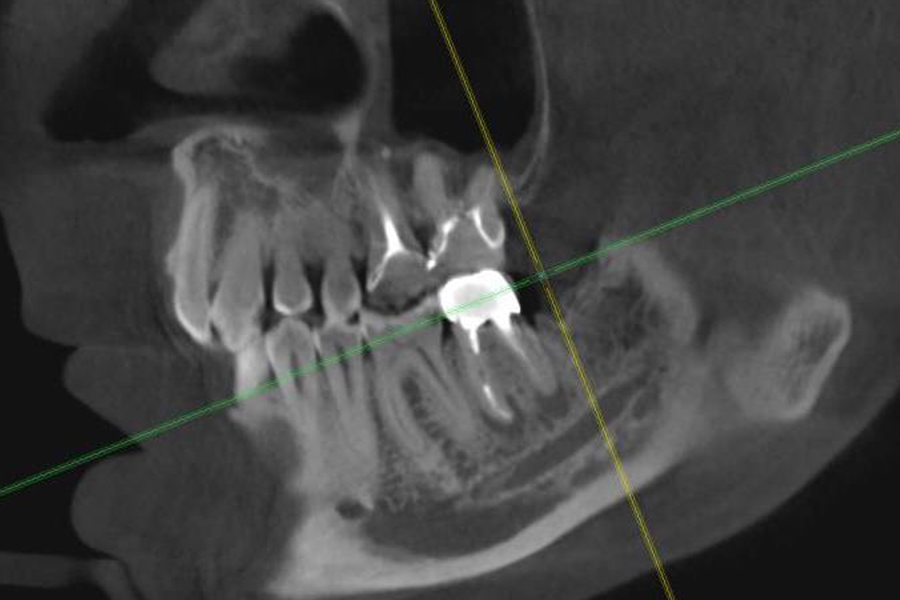

Результат

По результатам КЛКТ мы наблюдаем положительную динамику, уменьшение очага деструкции костной ткани